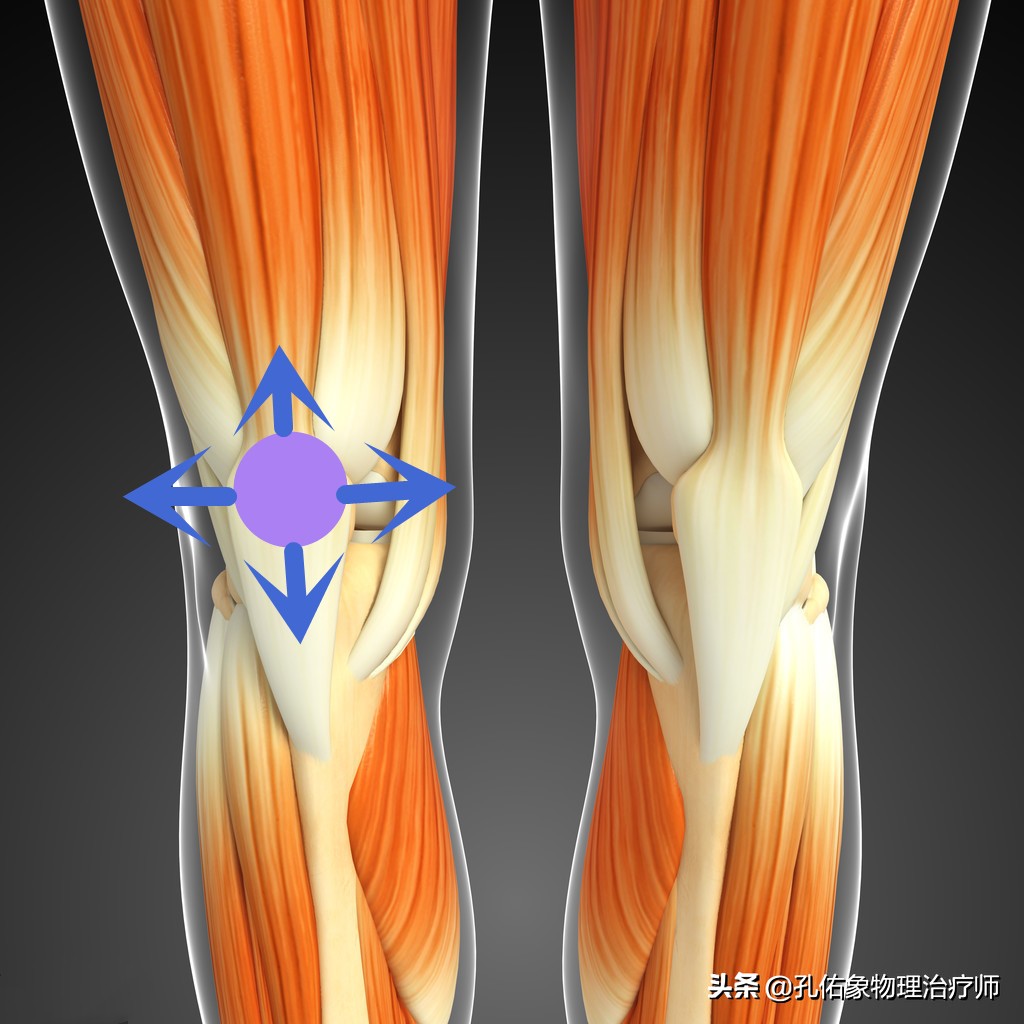

• 膝盖骨的研磨试验检查

膝关节痛骨性关节炎的治疗方法,膝骨性关节炎的手法治疗视频

检查时使膝盖骨与其相对应的大腿骨髁间关节面互相挤压研磨或上下左右的滑动,是否伴有粗糙的摩擦感、磨砂音和患肢膝关节的疼痛不适。